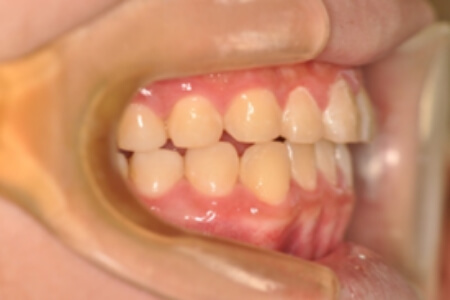

すきっ歯・正中隔離(非抜歯)【2286】

初診時

年齢

16歳 性 別 男性

治療内容の詳細 初診時16歳の男性で、前歯のすきまを気にされ、来院されました。

検査の結果、アングルⅢ級不正咬合と診断しました。

治療としては、非抜歯の上、マウスピース矯正装置(インビザライン)で配列を行いました。顎間ゴムの協力もあり、咬み合わせがきれいに改善されました。

治療期間は1年11か月でした。